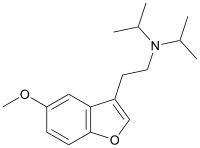

A number of related compounds are known, with a similar structure but having the indole core flipped and/or replaced with related cores such as indoline, indazole, benzothiophene, or benzofuran. These similarly are primarily active as agonists at the 5-HT2 family of serotonin receptors, with applications in the treatment of glaucoma, cluster headaches or as anorectics.

Dimemebfe | 2-(5-Methoxy-1-benzofuran-3-yl)-N,N-dimethylethanamine | 140853-58-3 |